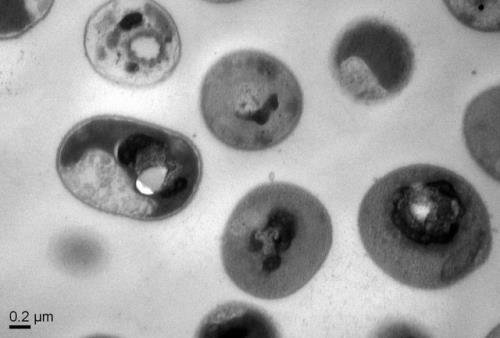

ثبت اولین مرگ بر اثر مبتلاشدن به ویروس خطرناک ماربورگ در آفریقا